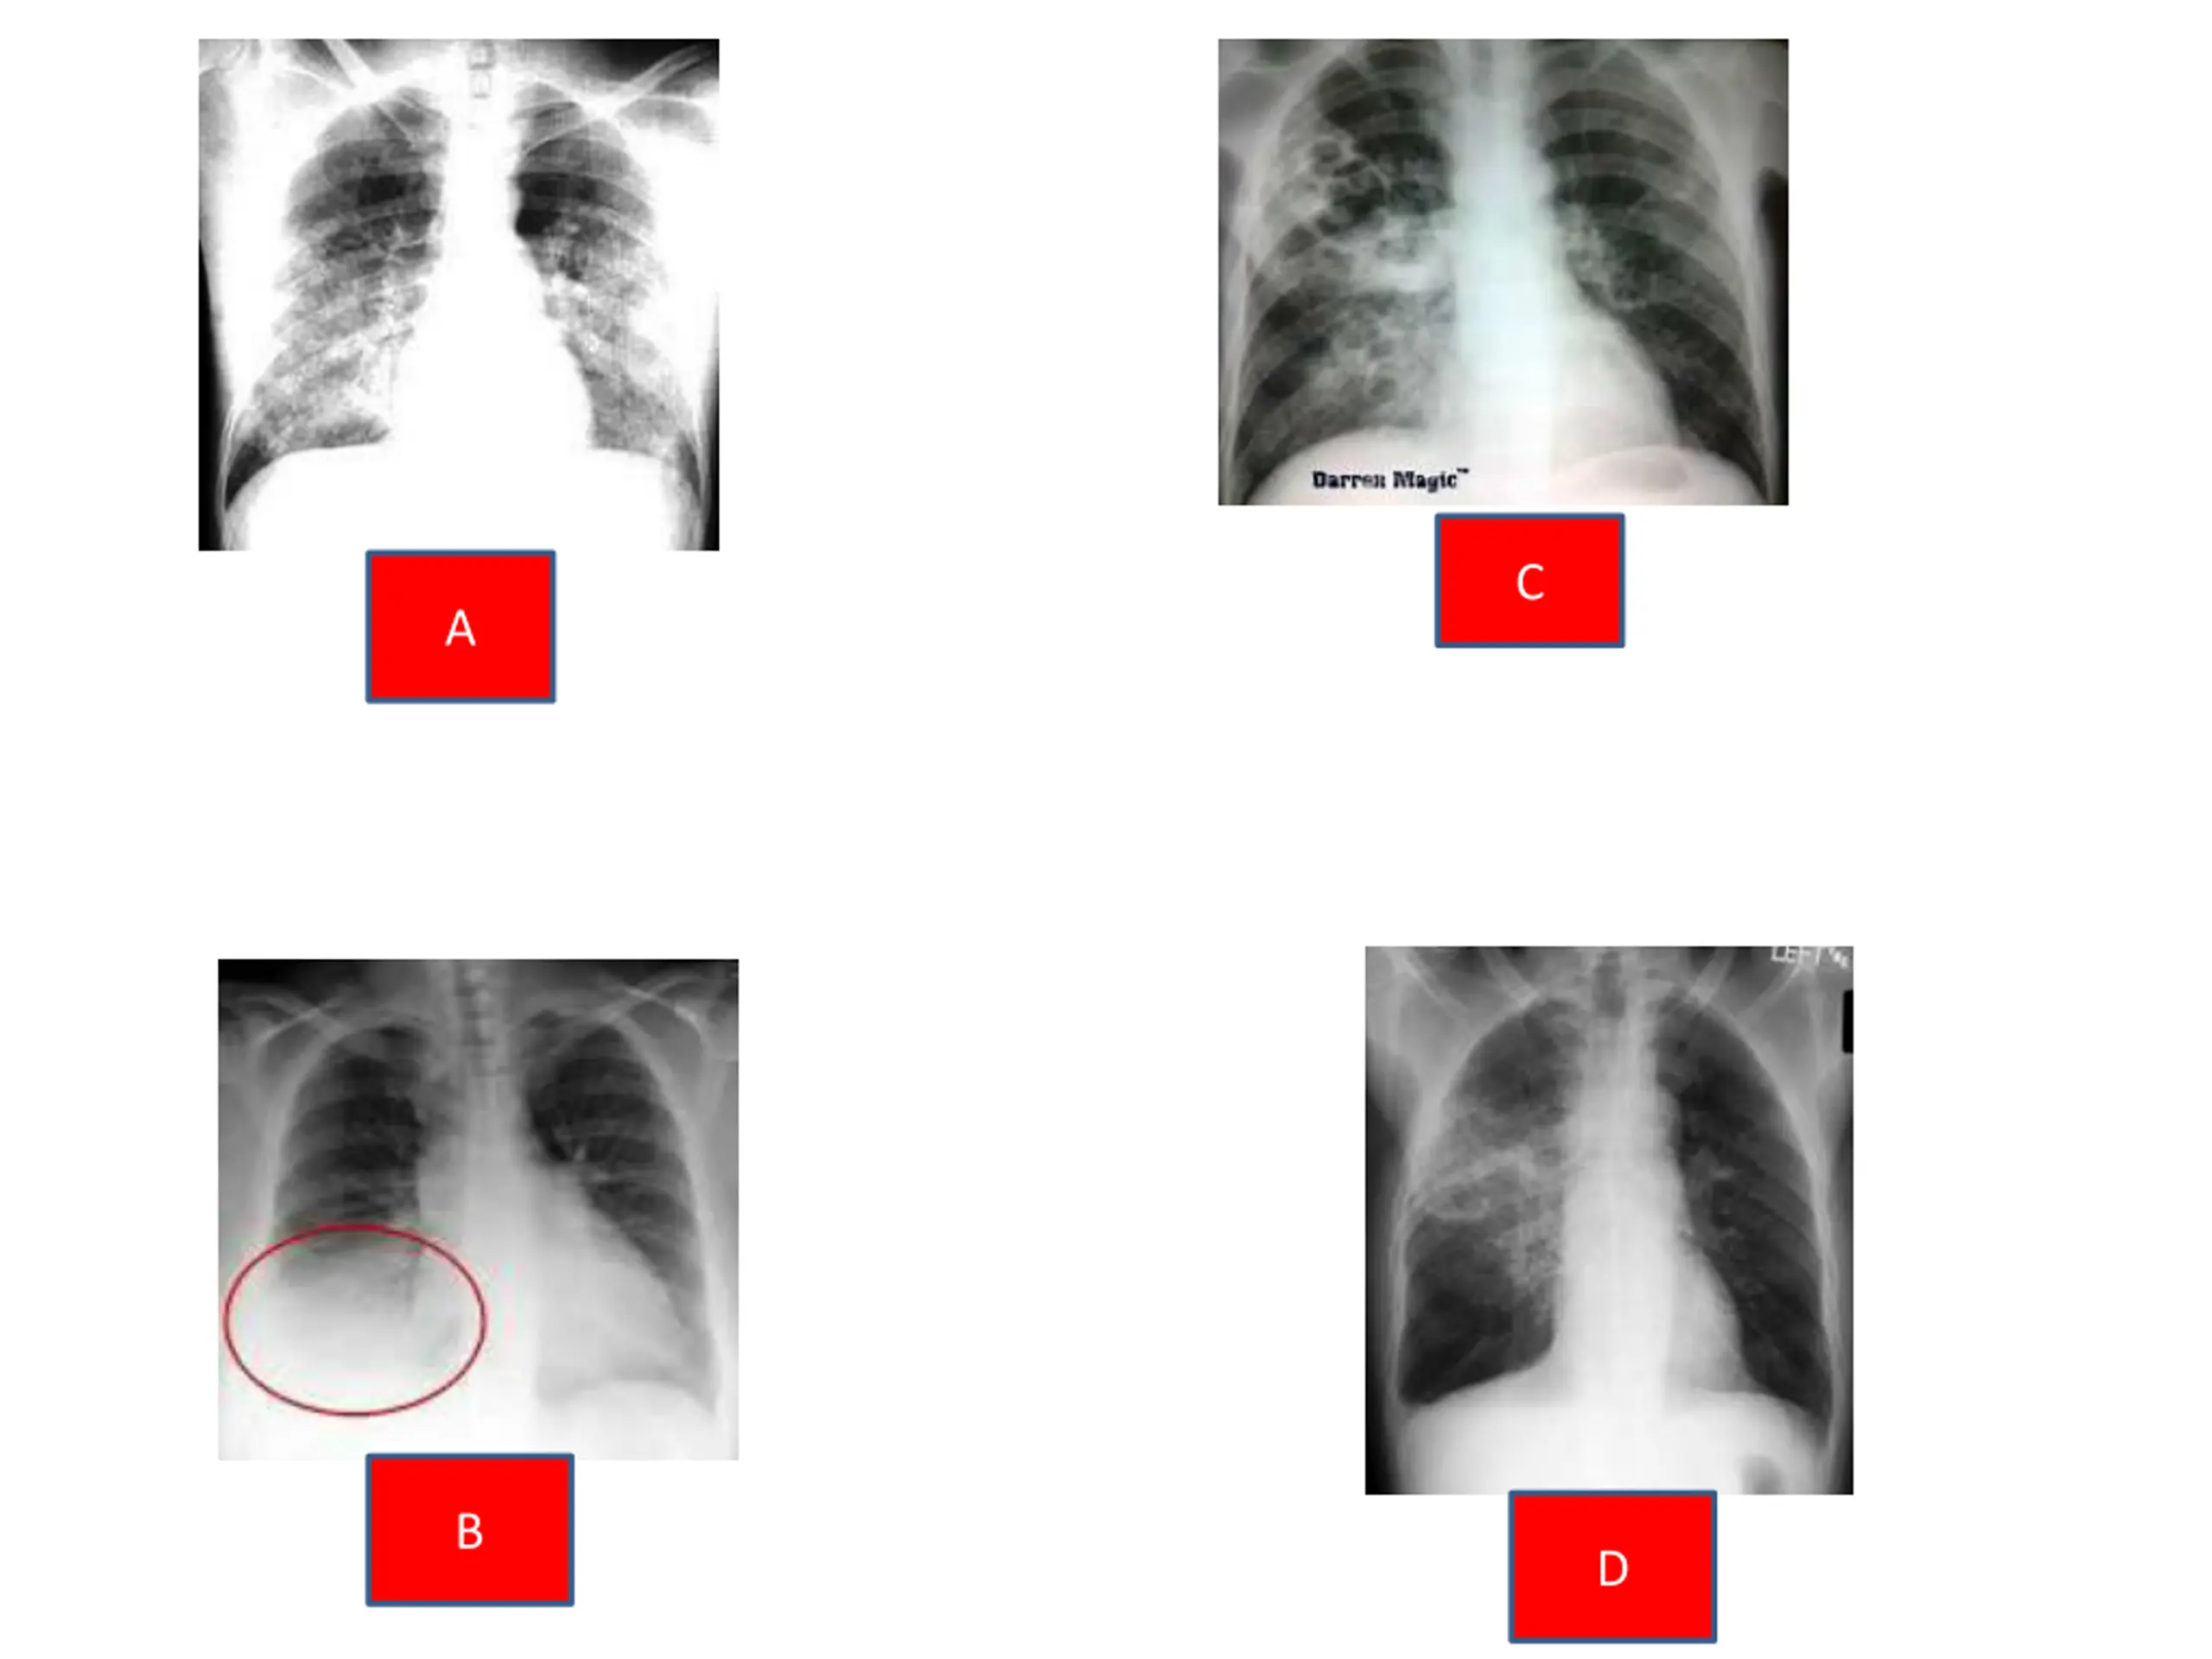

Radiological investigations in patients with CAP In bronchopneumonia patchy non homogenous mostly basal opacity, while in lobar pneumonia, a homogeneous opacity localised to the affected lobe or segment usually appears within 12-18 hours of the onset of the illness. Clinical-radiographic dissociation is seen often in patients with Mycoplasma pneumoniae or viral pneumonia. Chest radiographs of patients with Mycoplasma infection often suggest a more serious infection than does the appearance of the patient or the physical examination. The converse is true in patients with Pneumocystis carinii infection, who may appear quite ill despite normal or nearly normal chest radiographs. This may also be true early in the course of acute bacterial pneumonias, when pleuritic chest pain, cough, purulent sputum, and inspiratory crackles may precede specific radiographic findings by many hours. when the patient's symptoms and signs point to this diagnosis. A "negative" radiograph can never rule out the possibility of acute bacterial pneumonia Although the pattern of infiltration may establish a specific microbiologic etiology, chest films are most useful for providing essential information on the distribution and extent of involvement,as well as potential pneumonic complications like para-pneumonic effusion Standard posteroanterior and lateral chest radiography are mandatory .

C A B D